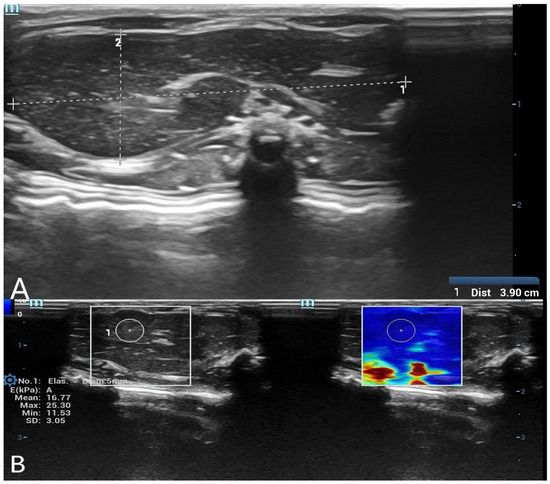

SWE measurements were acquired by a radiologist with over 8 years of experience in ultrasonography. A circular region of interest (ROI) with a diameter of 5 mm was placed centrally within the liver parenchyma, and a 3 mm ROI was used for the spleen parenchyma. ROIs were placed carefully in homogeneous tissue areas, avoiding visible ducts, vessels, or peripheral artifacts. The measurement protocol was standardized based on consensus among three radiologists before the study began. At each time point, three separate measurements were obtained and averaged. Only SWE maps without significant artifacts were included in the analysis. SWE results were recorded in kilopascals (kPa), and minimum, maximum, mean, and standard deviation (SD) values were calculated for each organ (Figure 1 and Figure 2).

Figure 2. (A) B-mode ultrasound measurement of spleen long and short diameters. A grayscale ultrasound image illustrating the measurement of spleen long and short diameters using electronic calipers. These dimensions were used to evaluate postmortem organ changes. (B) Shear wave elastography (SWE) measurement of spleen stiffness with a 3 mm region of interest (ROI). The left panel presents the grayscale ultrasound image of the spleen, while the right panel contains the SWE color-coded stiffness map. A 3 mm circular ROI is positioned within the spleen tissue to assess postmortem stiffness changes.